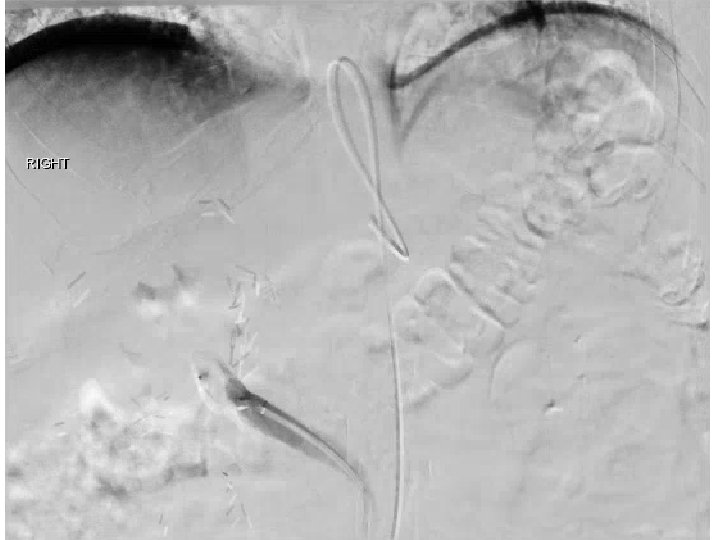

SIRT